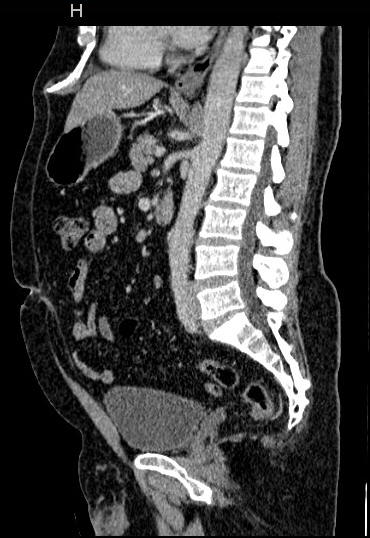

An abdominal CT scan offers images of the internal organs,

bones, soft tissue and blood vessels of the belly area. This procedure is

typically used to help diagnose the cause of abdominal or pelvic pain and

diseases of the internal organs, small bowels and colon. It is also

performed to guide biopsies and drain abscesses, plan for and assess the results

of surgery and stage, plan and properly administer radiation treatments for

tumours.